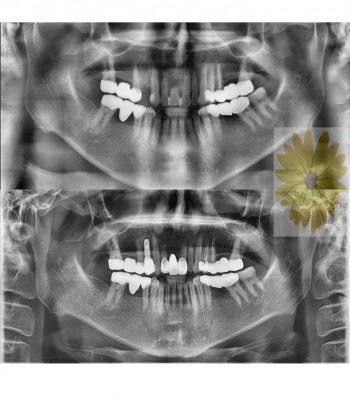

민들레치과 치료 전후사례